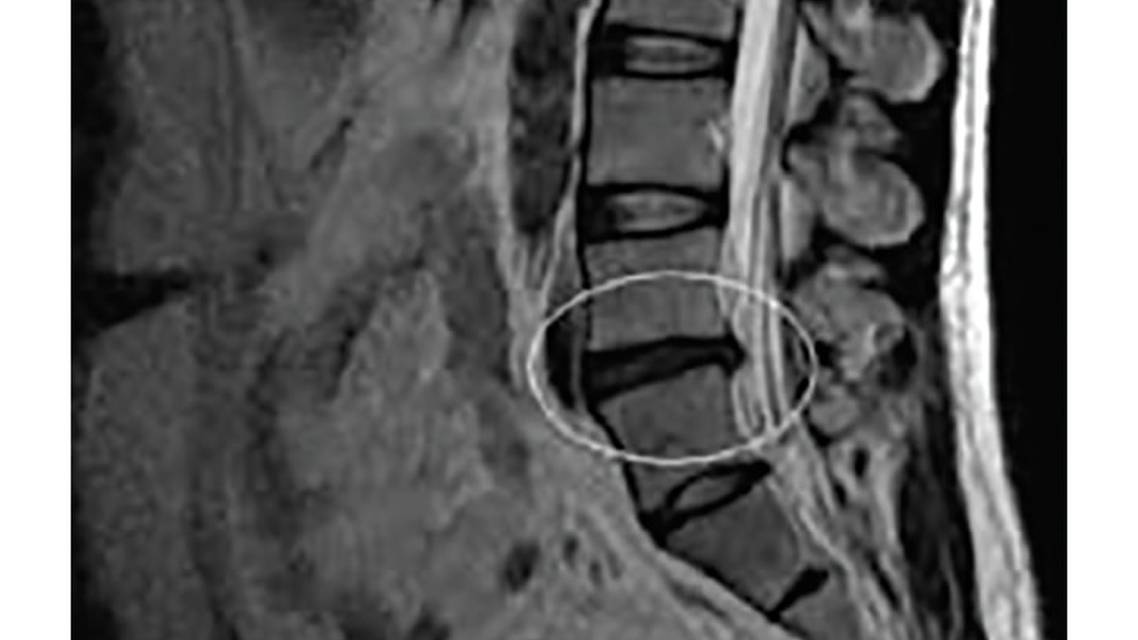

Maggie was diagnosed with acute lumbar radiculopathy.

With an acute lumbar radiculopathy, treatment is more conservative for the first 6 weeks. Most people will improve during this time independent of treatment because disc herniations often regress over time.11 The severe pain experienced can be caused by inflammation of the nerve root and possible irritation of the dorsal root ganglion, leading to pain in a dermatomal pattern.12 During this period, oral corticosteroids can be prescribed, and have been shown to improve functional status significantly but often do not relieve pain sufficiently.13

Once pain is subacute and even chronic in nature, injection therapies may be considered. The most common injections performed are epidural steroid injections, either with particulate or nonparticulate corticosteroids and local anesthetic. Both particulate (eg, triamcinolone, methylprednisolone) and nonparticulate (eg, dexamethasone) corticosteroids can help alleviate radiculitis. There may, however, be longer-lasting relief with the use of particulate steroids.14 There are certain safety considerations with particulate corticosteroids. For example, inadvertent intra-arterial injection of particulate steroid can result in an embolic effect that may cause neurologic deficits, including paralysis.14 With regards to interlaminar versus transforaminal approaches for the injection, it is generally recommended that a transforaminal epidural steroid injection can provide short-term (2-4 weeks) pain relief in some patients with a lumbar disc herniation and radiculopathy.11 In general, there is insufficient evidence to support either injection approach over another.11